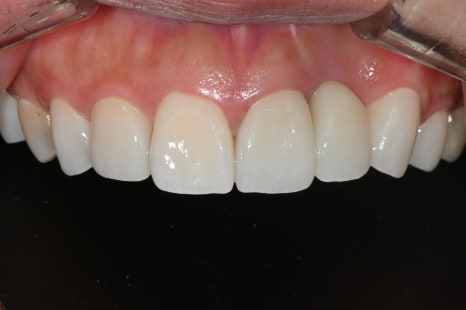

Left photo: This is the front view after treatment. It blends harmoniously with the adjacent teeth, completing a front tooth line that allows the patient to smile brightly.

“After treatment, the curve, brightness, and even the gum margin of the teeth harmonize naturally, creating a softer and healthier impression.”

In this treatment, a total of 8 prosthetics were replaced overall, including the upper front teeth and premolars.